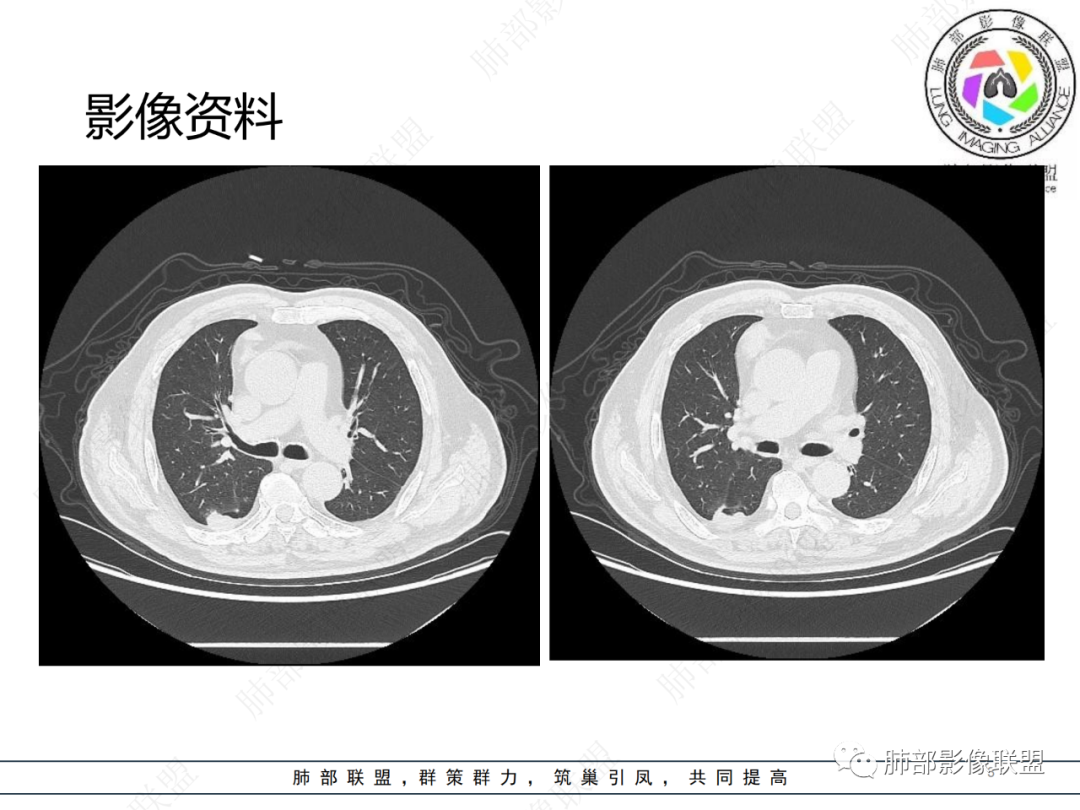

老年男性,体检发现纵隔占位,胸部CT检查所见,前纵隔多发软组织结节或肿块,右侧胸膜结节,密度均匀,边缘分叶,未见明显坏死,强化尚明显均匀强化,冠状位第1张图,左侧膈肌连续性中断,未见明确脾脏显示,可以考虑转移?异位组织(异位脾脏)?如果左侧膈肌确实断裂且无脾脏那么考虑异位脾脏可能大,或者代偿的淋巴结,再有鉴别神经源性肿瘤,入鞘瘤,不过鞘瘤一般会有ab区,这个病例没有。

前纵隔结节及右肺下叶背段胸膜下结节,增强扫描明显强化,所示图像未见脾脏,考虑异位脾并神经源性肿瘤或孤立性纤维瘤,鉴别胸腺瘤并神经源性肿瘤或孤立性纤维瘤。

右前纵膈不规则软组织密度影,密度均匀,分叶,中度强化,心包受侵,右侧胸膜不规则结节,明显强化,考虑胸腺瘤B2或B3型伴胸膜转移,鉴别胸腺癌

老年男性,前纵隔软组织结节灶,分叶状,偏于右侧,右侧胸膜亦可见结节灶,考虑高危型胸腺瘤或胸腺癌侵及胸膜

老年男性,右前纵隔结节,右侧胸膜下小结节,增强前纵隔结节中度欠均匀性强化,首先考虑胸腺瘤(B2、3级),鉴别纵隔神经内分泌肿瘤,比如类癌。

男,76岁,前纵膈偏右结节,形态较规则,浅分叶,富血供,增强明显不均匀强化,强化峰值在动脉期,考虑B2,3胸腺瘤,鉴别胸腺类癌(一般强化峰值在静脉期),胸腺鳞癌(形态不规则,边缘不清晰,多侵犯邻近大血管)

肺盟病例,右前纵膈占位,边缘有钙化,强化显著,临近心包有少许积液。考虑胸腺类癌可能,右肺胸膜下病灶考虑炎性肉芽肿可能。